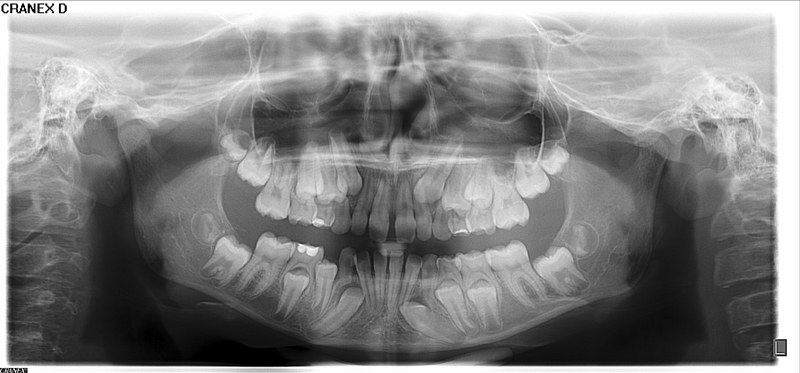

Radiografia Panorâmica